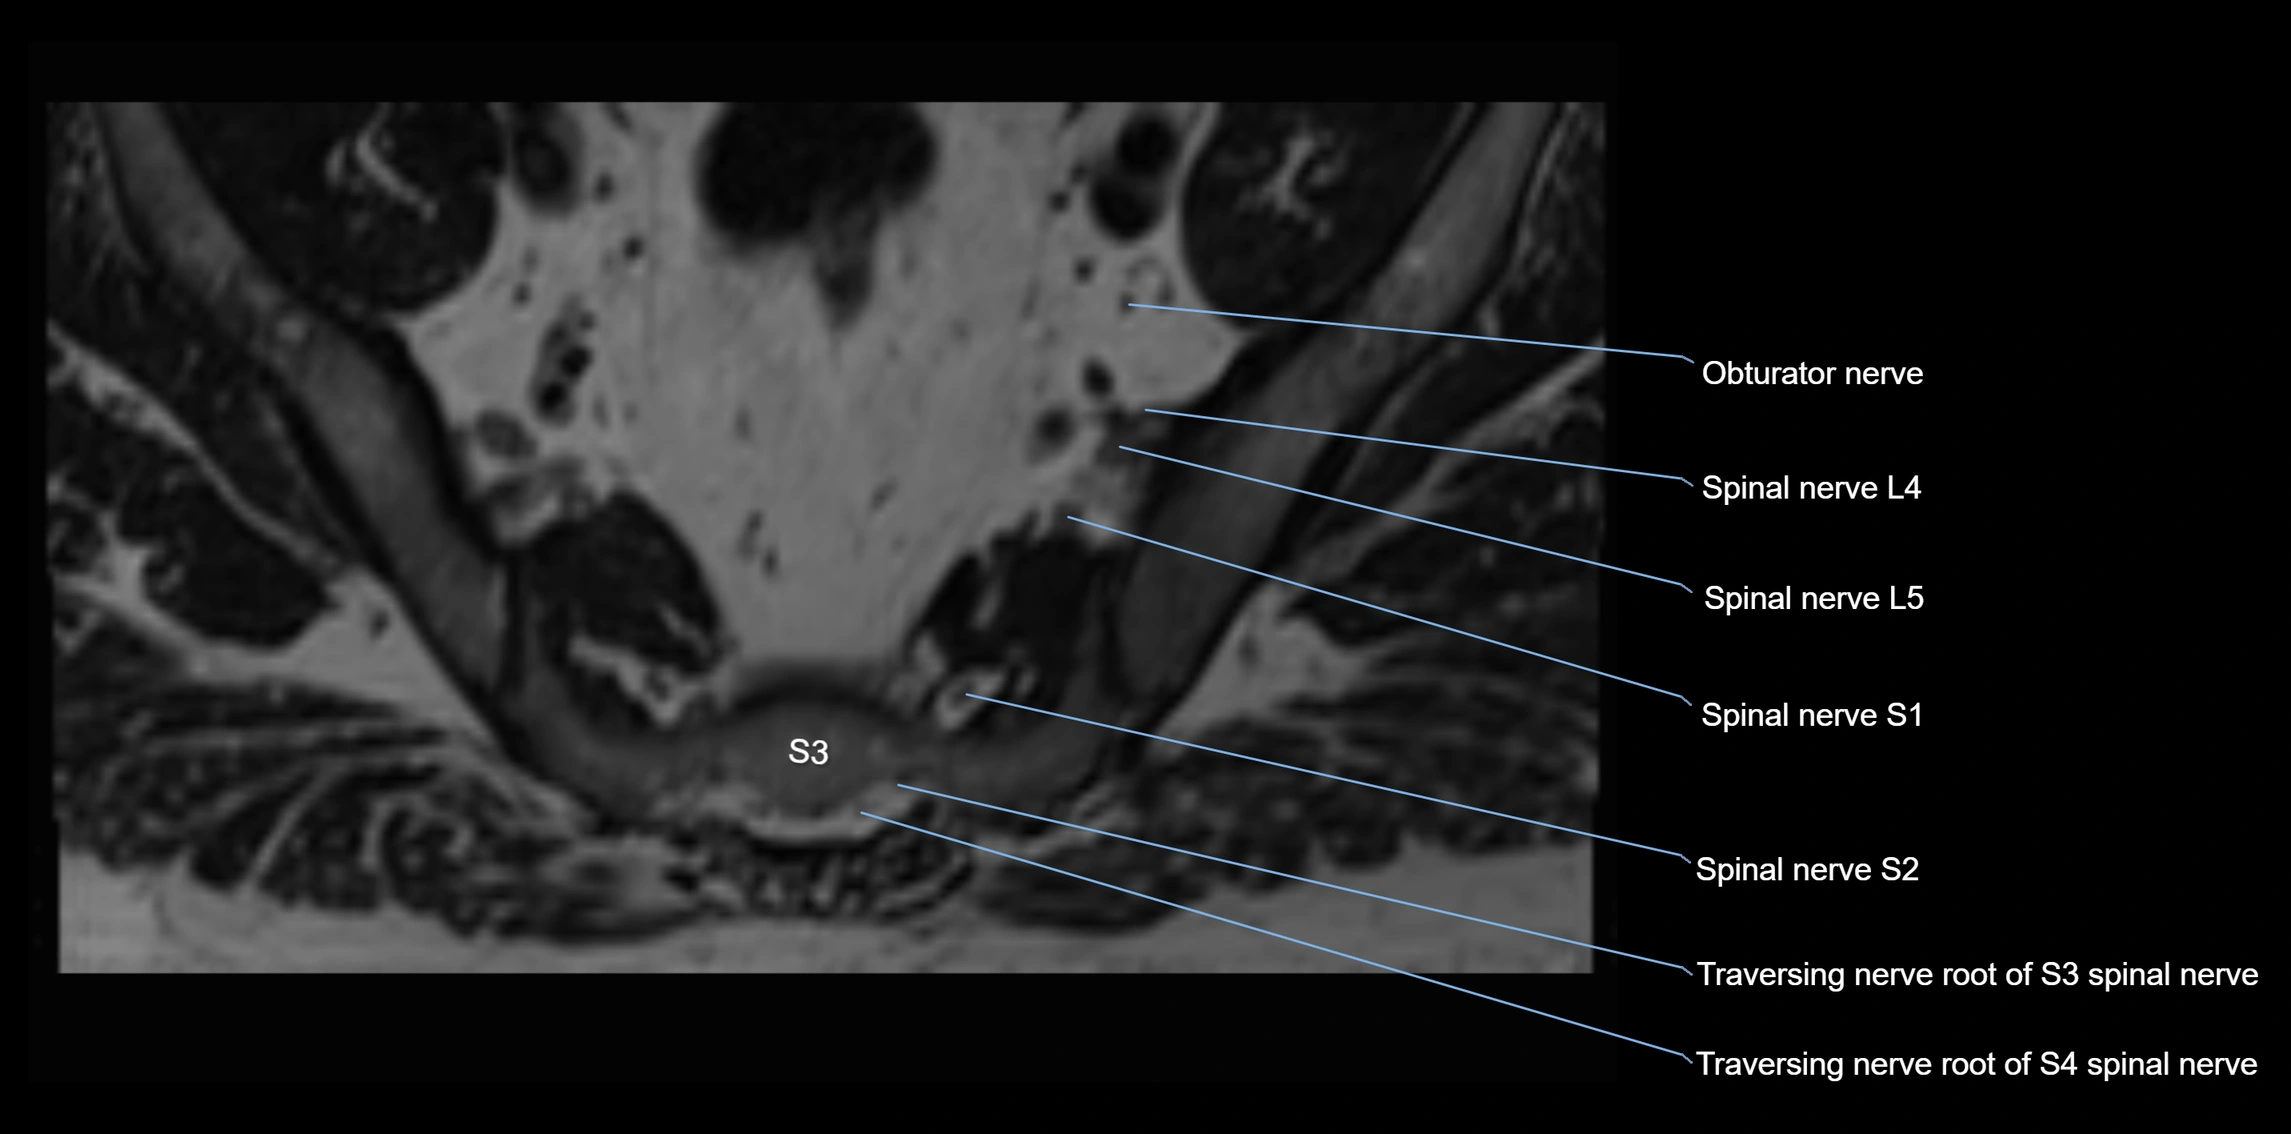

MRI image

image